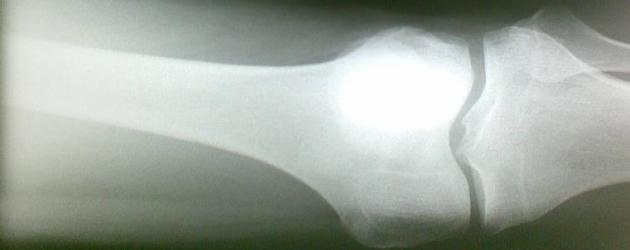

Beeld: Mikko Koponen/CC BY 2.0